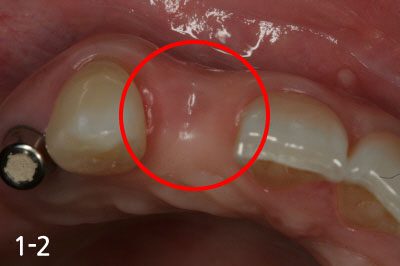

Gum bone is depressed after extraction